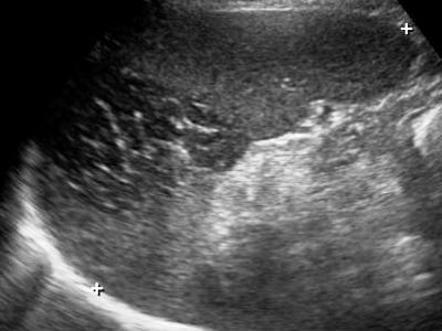

Mirizzi SYndrome

impacted stone in the cystic duct or GB neck

presence of two tubular structures representing the bile duct above the level of the cystic duct

Mirizzi SYndrome

impacted stone in the cystic duct or GB neck

presence of two tubular structures representing the bile duct above the level of the cystic duct